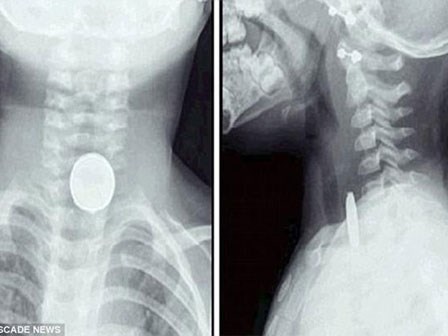

Bé gái 8 tuổi nuốt cục pin vào bụng, hành động của bà nội suýt làm cháu mất mạng

Chỉ một sơ suất nhỏ và sự thiếu kinh nghiệm xử lý của bà nội đã khiến tính mạng của bé gái 8 tuổi bị đe dọa.

Bé 2 tuổi suýt tử vong vì nuốt phải cục pin rất phổ biến trong đồ chơi trẻ em

Một bà mẹ đã đưa ra lời cảnh báo cho các bậc cha mẹ trong dịp Giáng sinh này khi con gái 2 tuổi của cô suýt tử vong vì nuốt phải một cục pin nhỏ xíu.